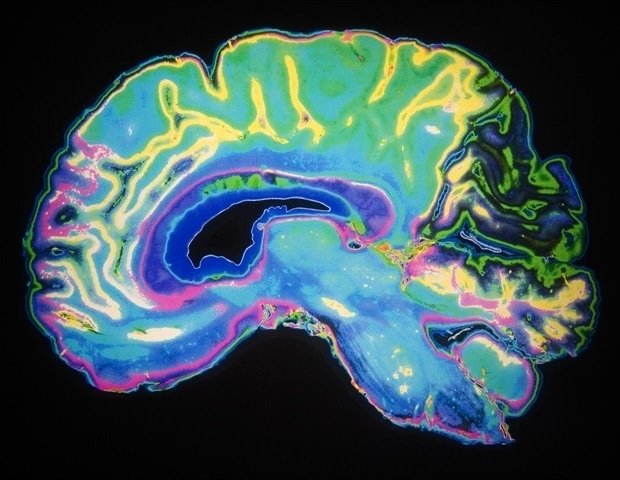

Understanding how the brain works requires more than studying single regions in isolation. The cerebral cortex relies on long-range connections that link specialized areas into coordinated networks. But scientists didn’t have the tools to selectively turn these specific connections “on” or “off” in the animal models that most closely resemble the human brain.

Using a sophisticated virus- and light-based technique called optogenetics, the research team was able to target only the neurons that connect one brain region to another, activating or silencing the same cells on demand. Optogenetics is a method of using light to control cells that have been genetically modified to respond to light. Neuroscience allows researchers to selectively activate or inhibit specific neurons.

These discoveries represent an important advance, as they allow scientists to manipulate individual long-range brain circuits with much greater precision than previously possible. Researchers can now isolate a single communication pathway within the complex and highly interconnected cortex, rather than broadly affecting many nearby cells.